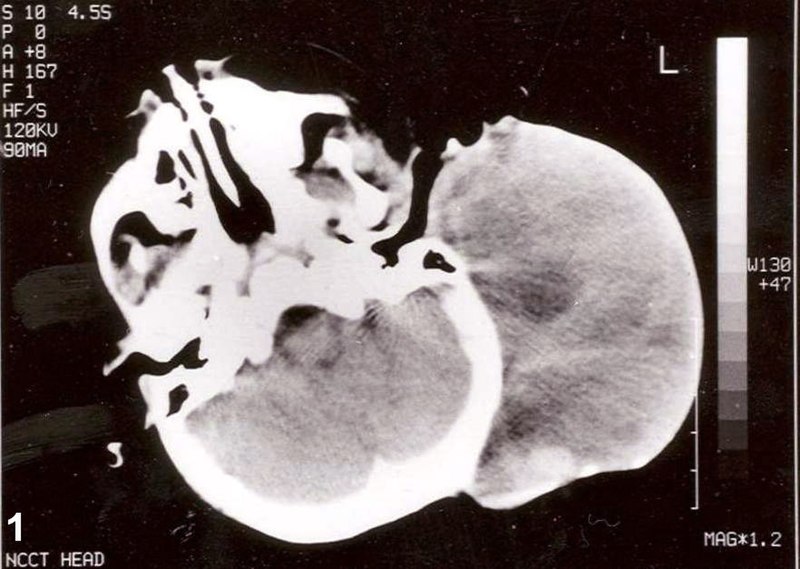

Choroba ta charakteryzuje się szybkim wzrostem i tendencją do przerzutów, co sprawia, że wczesne rozpoznanie i leczenie są kluczowe dla poprawy rokowania pacjenta. Objawy mogą obejmować ból, obrzęk lub guz w okolicy dotkniętej nowotworem, a także problemy z funkcjonowaniem narządów, w których nowotwór się rozwija. W przypadku mięśniakomięsaka prążkowanokomórkowego istotne jest przeprowadzenie dokładnych badań diagnostycznych, takich jak tomografia komputerowa czy rezonans magnetyczny, aby ocenić stopień zaawansowania choroby i planować dalsze leczenie.